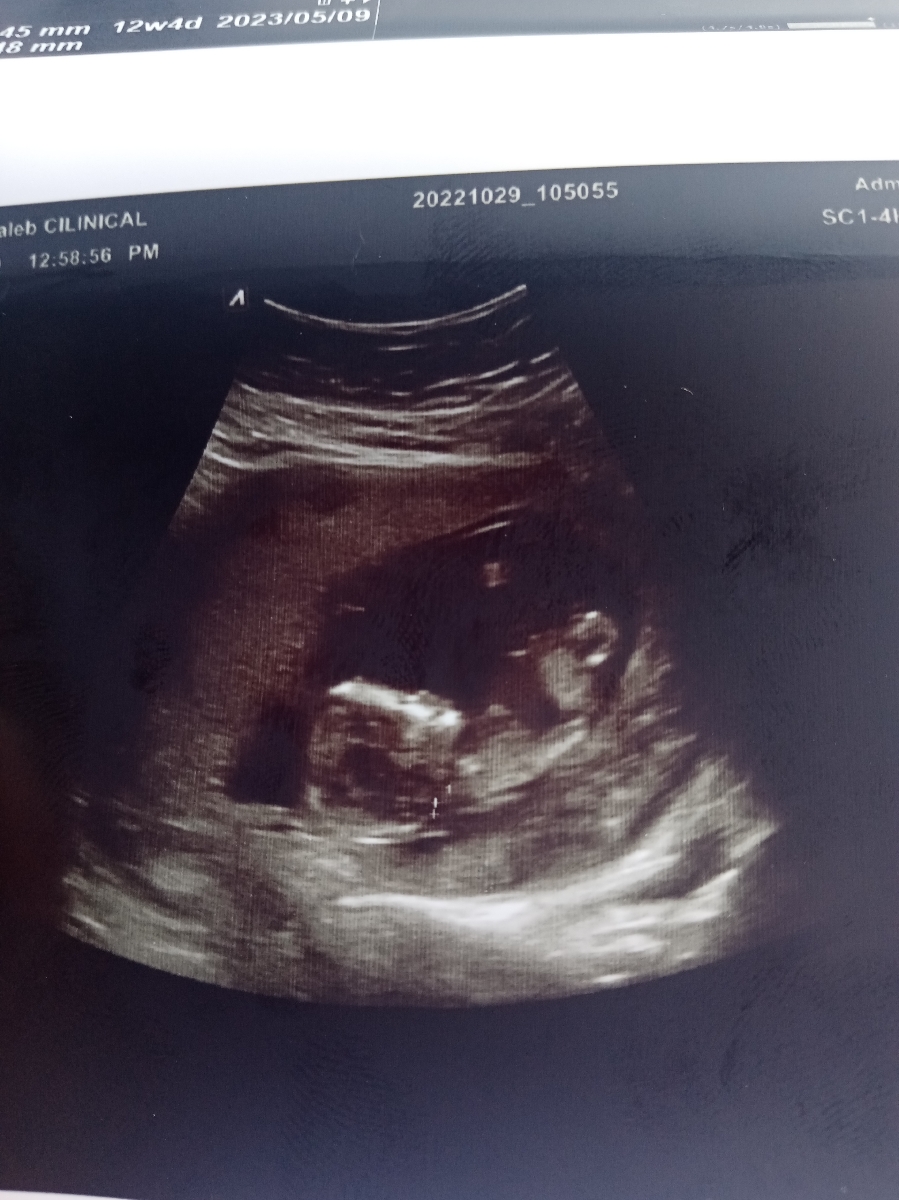

دوستان من قرار بود فردا برم سونو خخخخ امروز خلوت بود منشی گفت بیا امروز برو دیگه. دیگه رفتم الحمدالله همه چی خوب بود آزمایش غربال اول رو هم دادم تا هفته دیگه جوابش آماده میشه ان شاء الله اونم سالم باشه.

حدسی چیزی میتونید بزنید. دکتر هیچی نگفت

. حدسی بگین 😍😍😍😍😍😂

چه قشنگ داره میخنده☺️

من فکرکنم دختره

به سلامتی باشه عزیزم 😍خداروشکر خیالت راحت شد به نظرم به پسر میخوره نی نی

بنظر من پسره😁

بنظر من دختره

سلام گلم خداروشکر که همه چی خوبه بنظرم نینی دخمله البته هرچه باشه مهم سالم بودنشه خیلی واست خوشحال شدم

وای خدا جوجه رو ببین😍😍😍😍عزیزم خدا حفظش کنه

به نظرم پسره

وای من مردم برای حالت صورتش😍

از همین الان مهربونه😍 دختره بنظرم❤